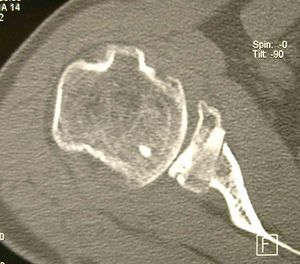

Computed Tomography (CT) Scan

Computed tomography (CT) scans also help the physicians to analyze the bony morphology of the shoulder joint. Before operative management, it is effectively imperative to assess for abnormalities in glenoid version (mean, 4.9 degrees in normal shoulders)[20] according to the Friedman technique,[21] posterior glenoid rim fractures or bone loss, and reverse Malgaigne (Hill-Sachs) lesions. These factors help determining the treatment strategies.